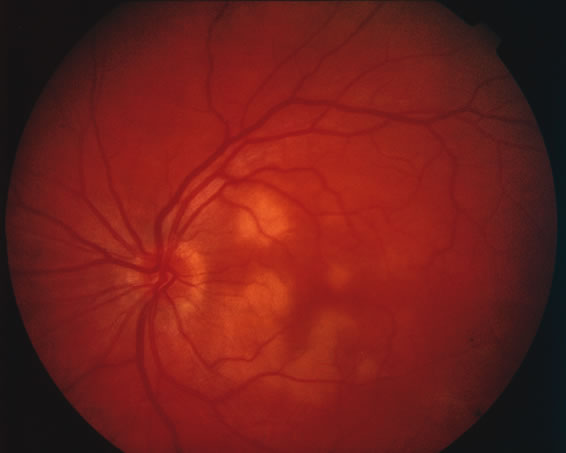

FUNDUS FINDINGS.

Acutely, there may be creamy white lesions in the posterior pole. These lesions tend to be deep and poorly demarcated. Sometimes these lesions may become confluent. The lesions clear by losing their yellow-white opacification and clearance occurs from centrally to the periphery. With time the lesions resolve leaving mottling of the retinal pigment epithelium (Figs. 5, 6, and 7).

Fig. 5. Fundus photograph showing the acute creamy lesions of a recent case of acute multifocal posterior placoid pigment epitheliopathy.

Fig. 6. Fundus photograph of the same case as in Figure 5. The findings at 1 month after the initial presentation now shows mild pigment clumping and mild retinal pigmentary atrophy.

Fig. 7. Fundus photograph of the same case as in Figure 5. The findings at 7 months following initial presentation show more pigment clumping and retinal pigment atrophy in small circular lesions.